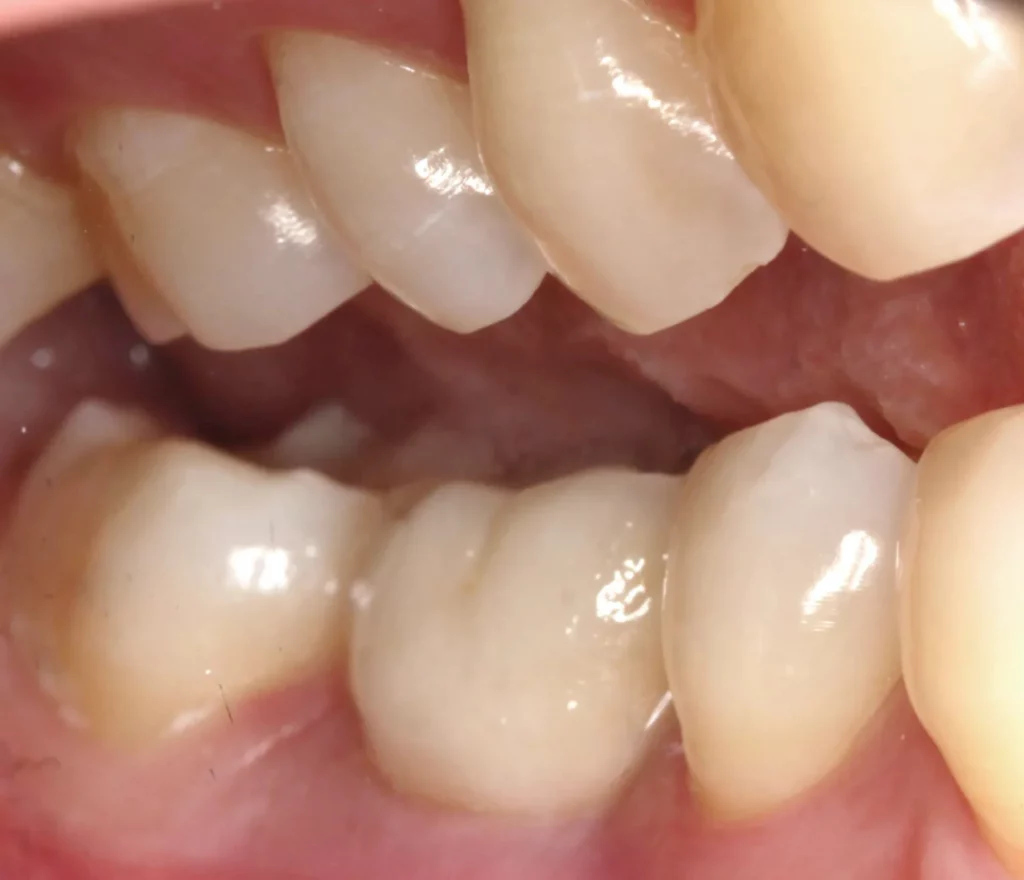

This woman had a badly broken down lower molar that had split apart and had been painfully abscessing for months. Unfortunately, it was beyond saving, and it was extracted. Keen to have the space restored, the patient opted to have an implant placed.

Below shows the crown fitted on to the implant post.